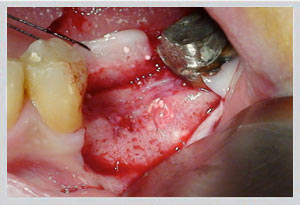

Upper jaw: GBR (guided bone regeneration) for moderate buccal defects; block bone grafting for larger volume requirements. Socket preservation at time of extraction prevents bone loss from occurring in the first place.

Lower jaw: Block bone grafting for severe buccal wall defects. Easy Graft Crystal (non-resorbable beta-tricalcium phosphate) for minor to moderate deficiencies. Socket preservation equally critical.

3. Graft Materials

Dr. Zarifeh's preferred protocol combines synthetic Easy Graft with autogenous bone chips — pairing the structural scaffold of a synthetic material with the biological activity of the patient's own cells. The selection is made individually per case based on defect size, location, and planned implant timeline.